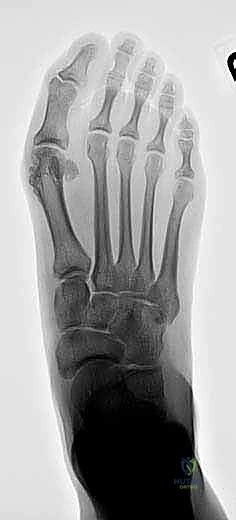

2. التصوير الشعاعي المتقدم

- الأشعة السينية مع تحمل الوزن (Weight-bearing X-rays): صور من الأمام، الجانب، والزوايا المائلة لتقييم زوايا العظام تحت تأثير وزن الجسم.

- تصوير السمسمانيات (Sesamoid view): لمعرفة ما إذا كانت العظام السمسمانية قد خُلعت من مكانها.

هذا المفصل هو ساحة المعركة الرئيسية. يربط عظم المشط الأول (First Metatarsal) بالسلامية الدانية (Proximal Phalanx) لإصبع القدم الكبير. في التشوه الأولي، ينحرف إصبع القدم نحو الخارج (Valgus)، وينحرف عظم المشط نحو الداخل (Varus). إذا لم يقم الجراح الأول بتصحيح الزاوية بين المشطين (IMA) بشكل كافٍ، فإن قوى المشي ستدفع الإصبع للتشوه مرة أخرى.

- عدم تصحيح زاوية (IMA) بشكل كافٍ: الفشل في تضييق المسافة بين المشط الأول والثاني بشكل كامل.